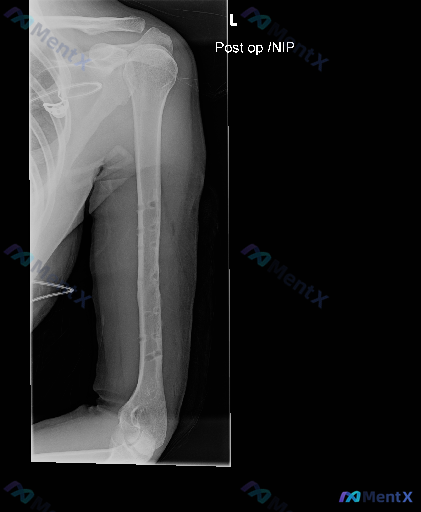

整理到一张左上臂(肱骨)正位X光的影像资料,大家先一起看看: - 影像显示左侧肱骨干髓腔内可见一排规则排列的圆形/类圆形透亮缺损影 - 影像上有标注文字“Post op / NIP” - 肱骨干整体形态连续,未见明显的急性骨折线、成角畸形或严重移位 - 骨质密度:皮质厚度尚可,未见明显的骨皮质破坏、...